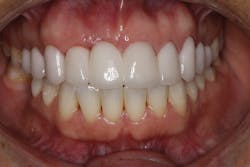

• site development to increase hard and soft tissue for pontic sites in fixed bridge prosthetics (figures 9–14);• correcting bone defects impinging upon anatomical structures after tooth extraction, such as oroantral communication (figure 18); and